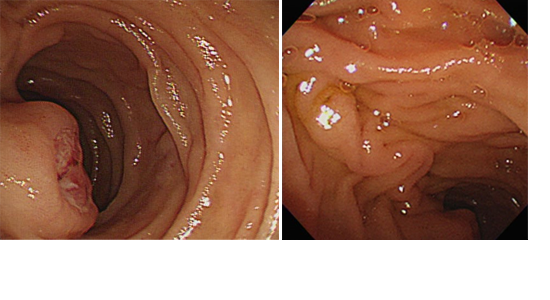

특이병력 없던 49세 남자가 일주일간의 흑색변과 노작성 호흡곤란 증상으로 응급실에 내원하였습니다. 이전 혈액검사 결과는 확인할 수 없었지만 혈색소가 7.5 g/dL로 감소되어 있었고 상부위장관 출혈이 의심되어 상부위장관내시경을 시행하였습니다. 상부위장관내시경상 급성 출혈 소견은 보이지 않았지만 십이지장 제2부에 점막하조직이 노출된 상피하병변이 관찰되었고 바터팽대부와의 위치관계를 파악하기 위해 시행한 측시경상 병변은 바터팽대부에서 2~3cm 정도 떨어진 원위부에 위치하는 것으로 확인되었습니다. [그림1]

[그림1] 상부위장관내시경상 십이지장 제2부에 궤양을 동반한 십이지장 상피하병변이 관찰됨.